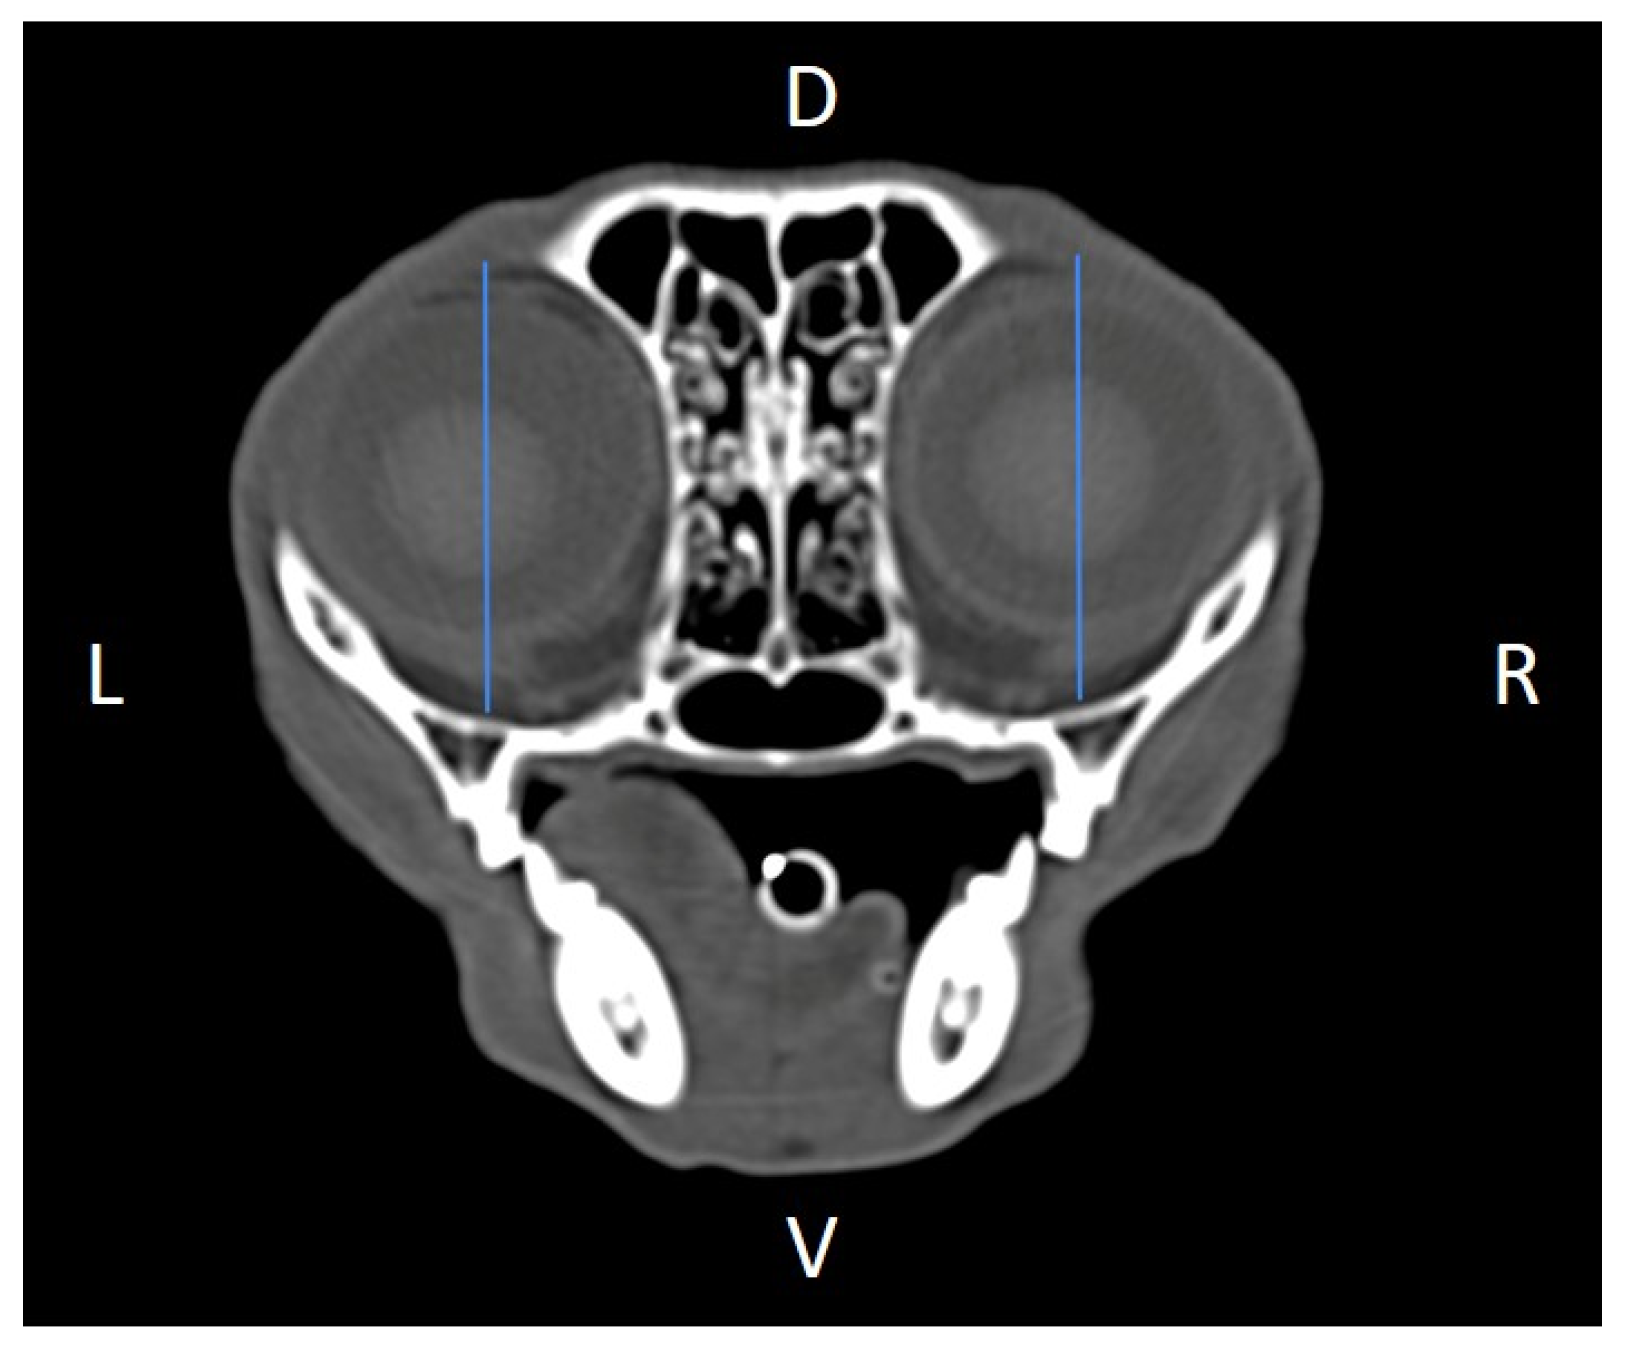

Linear morphometric parameters (Table 1) were obtained directly from CT images using HorosTM v3.3.6.dmg DICOM software with bone filters. Prior to measurement, all images were calibrated from pixels to millimeters. A preliminary study and prior training were conducted, to establish anatomical landmarks that would allow for the repeatability of the measurement methodology by J.F.R., A.R.S., S.A.-P. Recorded variables included infraorbital foramen major axis (Figure 2), minor axis (Figure 3) and length (Figure 4), distance between infraorbital foramina (DIF) (Figure 5), orbital height and width (Figure 6 and Figure 7), zygomatic arch width (Figure 8), skull width and length (Figure 9). Ratios were calculated to normalize for skull size. As preliminary results revealed adequate repeatability of measurements, and in order to reduce the analysis margin of error, two measurements of each studied parameter were performed. The measurements were performed by the same operator (to reduce interpersonal errors), and each measurement of each parameter was performed at different times, in order to reduce intrapersonal errors. Then, the arithmetic mean of the measurements was calculated.

Figure 3. Infraorbital minor axis (IFmA) measured at the left and right sides, on a transverse CT image (blue lines). D, dorsal, L, left, R, right, V, ventral.